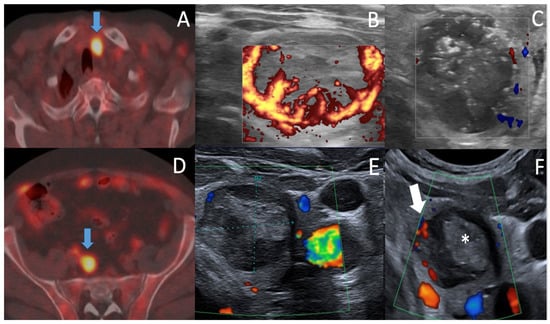

| Regrowth depiction in ablation area | None (13 months) | Medial part (0.3 mL, at 10 months) | |

| Color Doppler/MVI/CEUS | Color Doppler/MVI | ||